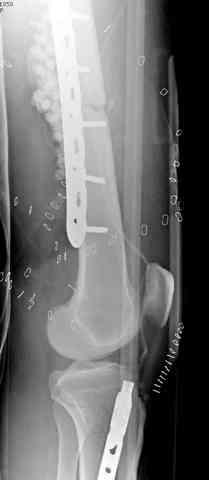

здесь случай с политравмой, перелом зафиксирован  наружным

фиксатором, после третьей irrigation&debridment фиксация бедра

пластиной с последующей кожной пластикой.

Вложение не в текстовом формате было извлечено…

Имя     : 7 open femur, tibia exfix 4.jpg

Тип     : image/jpeg

Размер  : 36517 байтов

Описание: отсутствует

Url     : http://weborto.net:8080/pipermail/ortho/attachments/20080516/ebe5bb74/attachment-0016.jpg